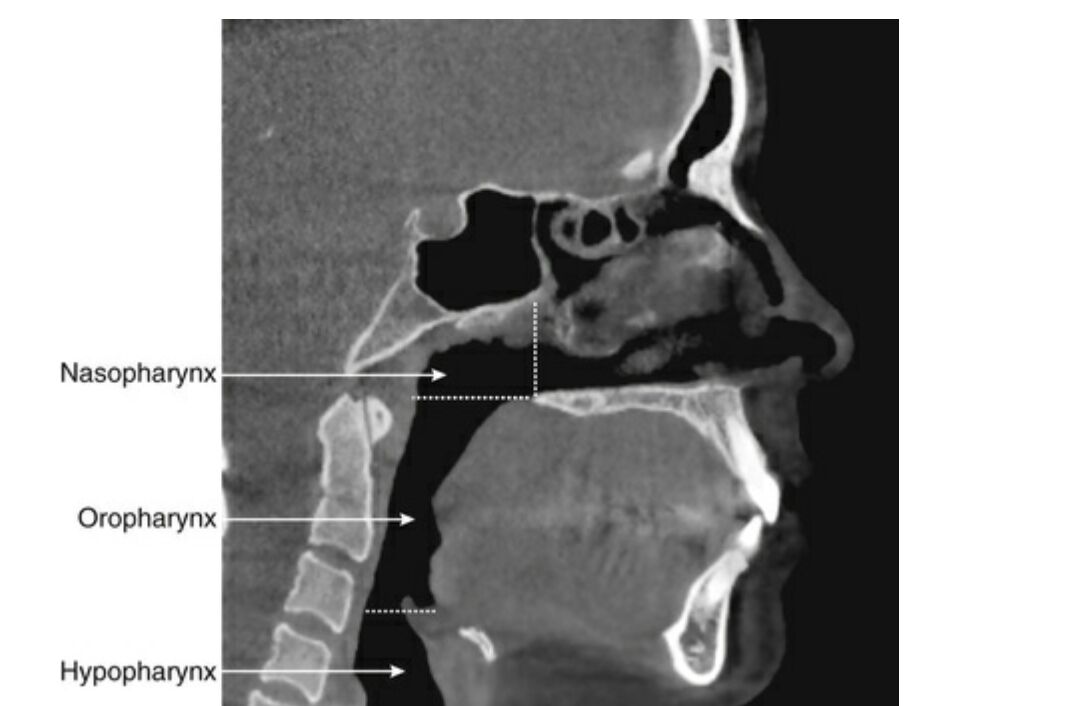

64.側顱X光片可用於評估呼吸道的狀況,下列何者最有可能是附圖中黑色箭頭所指的部位?

(B)鼻咽(nasopharynx)

(C)口咽(oropharynx)

(D)下咽腔(hypopharynx)